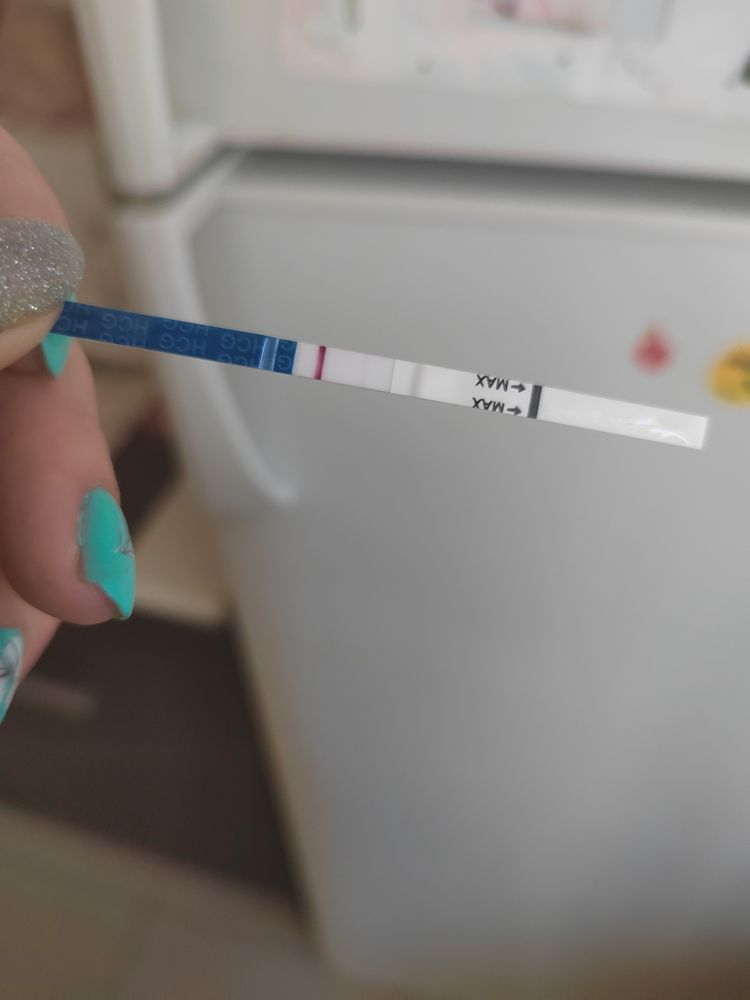

тесты пустые, я уже не надеюсь, думаю, что гормональный сбой, симптомов нет от слова совсем , но и пмс нет 🤷🏼♀️ знаю про позднюю овуляцию, кисты или наоборот надумывание признаков, и т.д)